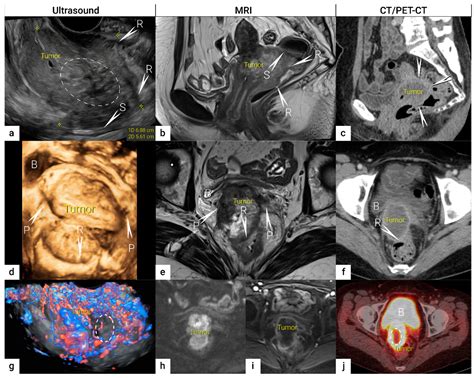

Cranio-cervical instability (CCI) - Algocells

Cranio-cervical instability (CCI) - Algocells